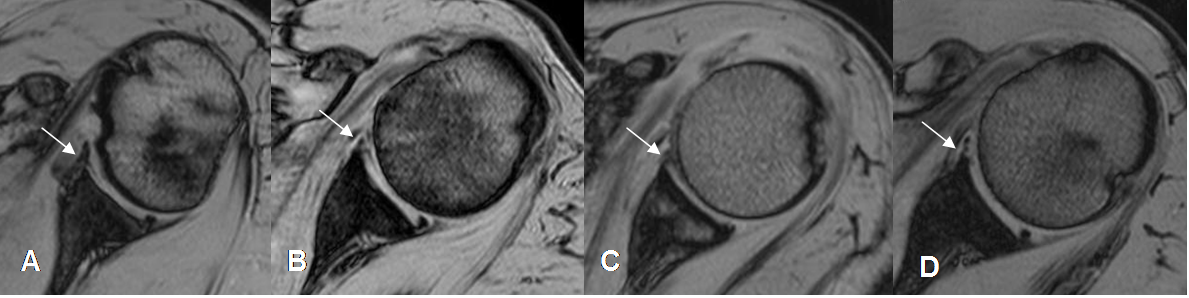

Los tendones de todos los grupos musculares, se aprecian como estructuras hipointensas en todas las secuencias, en relación con los sitios de origen e inserción. (Fig 12 a 17).

Fig 14. Tendón del subescapular normal.

A: RM axial en FFE y B: RM coronal en T1. Inserción en la tuberosidad menor. Su relación

con la apófisis coracoides (Flecha gruesa), ayuda a diferenciarlo del redondo menor.